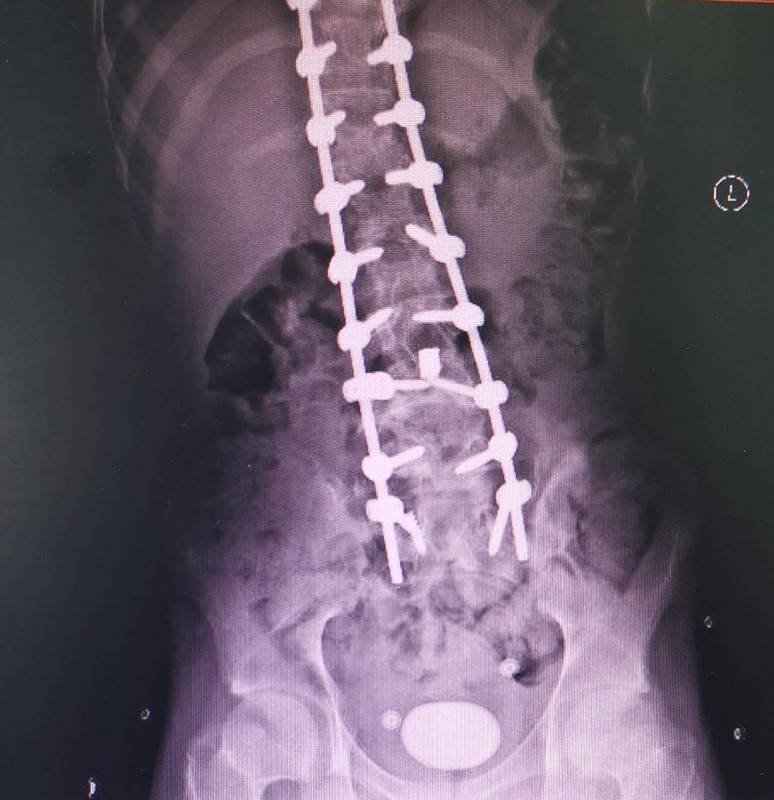

وبعد إجراء الفحوصات المخبرية والإشعاعية اللازمة لتشخيص الحالة، تبين وجود حصوة كبيرة في المثانة البولية، وبناء على ذلك، قرر الفريق الطبي إجراء تدخل جراحي، لإزالة الحصوة (بحجم 5 سم) من المثانة. فيما تكللت العملية بالنجاح واستقرت حالة المريض.